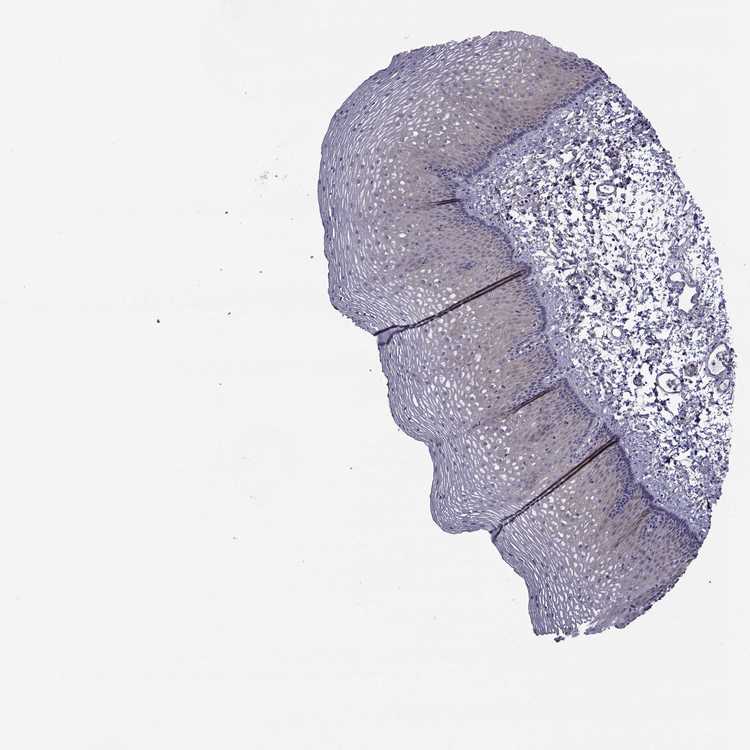

ESOPHAGUS - Antibody stainingi

Antibody staining in the annotated cell types in the current human tissue is reported as not detected, low, medium, or high, based on conventional immunohistochemistry profiling in selected tissues. This score is based on the combination of the staining intensity and fraction of stained cells.

Each image is clickable and will lead to virtual microscopy that enables deeper exploration of all samples and also displays staining intensity scores, fraction scores and subcellular localization as well as patient and tissue information for each sample.

Antibody HPA028521Antibody HPA029274Antibody HPA030240

Squamous epithelial cells Not detectedNot detectedMedium